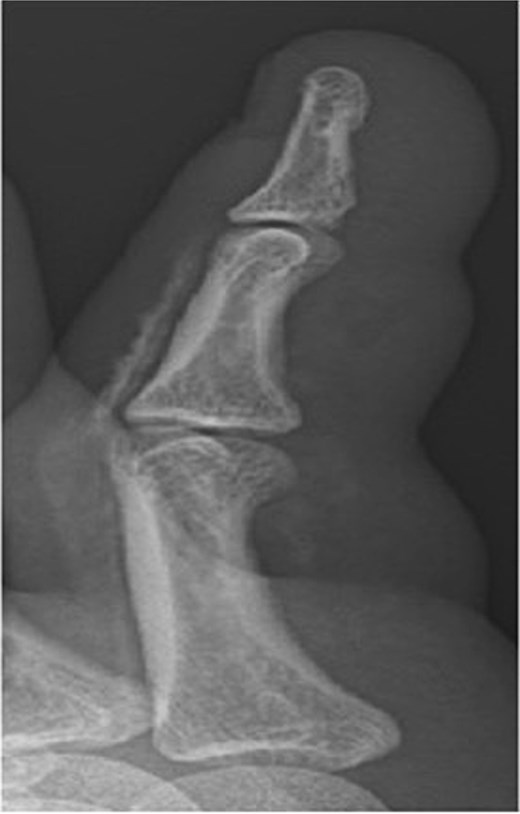

Initial presentation (Fig. 7) with accompanying X-ray (Fig. 8). Final image shows patients digit when he represented 2 months after original insult with a swollen finger and pus exudate (Fig. 9).

X-ray image of patient three showing injected material into surface of his digit, more obvious in the proximal portion.